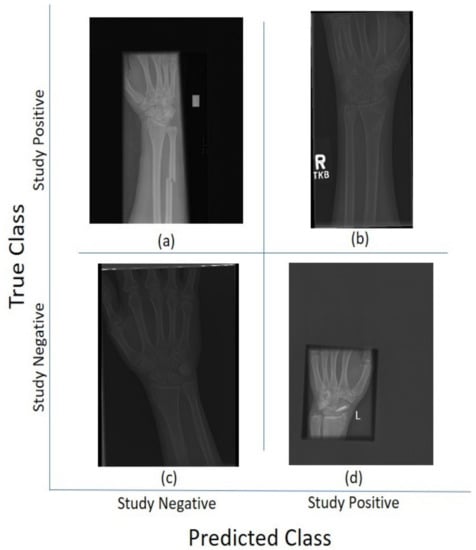

Class activation maps were obtained and overlaid on top of the representative images in Figure 1 and Figure 2. The CAMs obtained for ResNet50 are shown in Figure 7 and Figure 8, while those for Inception-ResNet-v2 are shown in Figure 9 and Figure 10. In all cases, the CAMs were capable of indicating the region of attention used in the two architectures applied. This is especially valuable for identifying where the abnormalities are in Figure 8 and Figure 10. While both models indicate similar regions of attention, Inception-ResNet-v2 appears to have smaller attention regions (i.e., more focused) than those in ResNet50. This may indicate a better extraction of features in the Inception-ResNet-v2 leading to better prediction results. Finally, the activation maps corresponding to Figure 5 and Figure 6 are presented in Figure 11.

The CAM provides a channel to interpret how a CNN architecture is trained for feature extraction and the visualisation of the CAMs in the representative images was interesting in several aspects. First, the activated regions in ResNet-50 appeared more broad-brushed than those of the Inception-ResNet-v2. This applied both to the cases without abnormalities (Figure 7 and Figure 9) and those with abnormalities (Figure 8 and Figure 10); second, the localisation of regions of attention by Inception-ResNet-v2 also appeared more precise than the ResNet-50. This can be appreciated in several cases, for instance the forearm that contains a metallic implant (b) and the humerus with a fracture (g); third, the activation on the cases without abnormalities provides a consistent focus in areas where abnormalities are expected to appear. This suggests that the network has appropriately learned regions essential to the correct class prediction.

Figure 11. Illustration of the class Activation Maps overlaid on the four classification results for (a,b) Postero-anterior and (c,d) Lateral views shown in Figure 5 and Figure 6 for ResNet 50 (a,c) and Inception-ResNet-v2 (b,d). In general Inception-Resnet-v2 presented more focused and smaller activation maps. It should also be noted that whilst for correct classifications, the highlighted regions are similar, for some incorrect classifications (c,d, top left and bottom right) the activations are quite different, which suggest that the architectures may not be confusing salient regions that are not related with the condition of normal or abnormal.